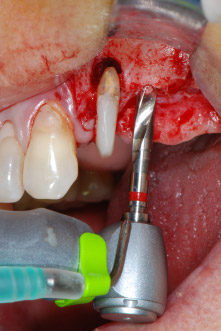

Elevación del seno maxilar y colocación del implante

Antes de colocar el implante, el tejido infectado del hueso alveolar ubicado en el lugar del implante y alrededor de los dientes del pilar se retiró con un inserto concebido en un principio para modelar huesos y recoger virutas óseas: Piezomed y el inserto B5 (figuras 6 y 7).

instrumento de raspado piezoeléctrico

Fig. 6: A continuación, el sitio quirúrgico se desbridó con un instrumento de raspado piezoeléctrico diseñado para recoger virutas óseas y modelar el hueso.

En el siguiente paso, los lechos del implante se prepararon en las posiciones 25 y 26 con instrumentos rotatorios, utilizando un contra-ángulo con un coeficiente de transmisión de 20:1 (WS-75 L, W&H), junto con el nuevo potente motor de implantes Implantmed de W&H (figuras 8 y 19).

La preparación final junto al seno se realizó de nuevo con un inserto piezoeléctrico (Piezomed S2).

Antes de la colocación del implante y tras la verificación de que la membrana de Schneider estaba intacta (figura 9), la base interna del seno se aumentó en las dos posiciones del implante con un material sustituto de hueso xenógeno (Bio-Oss, Geistlich Biomaterials) (figura 10).